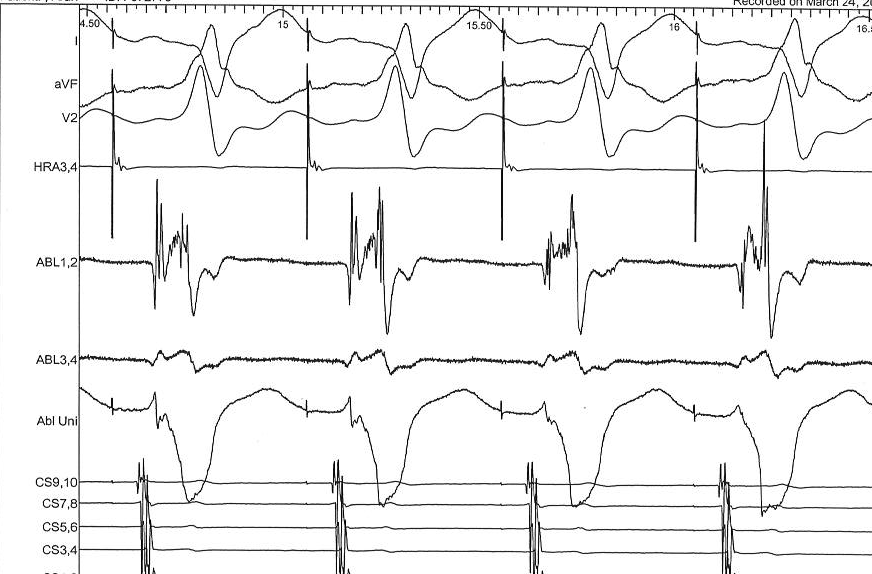

Recording / seeing the signals

unipolar_ap.png